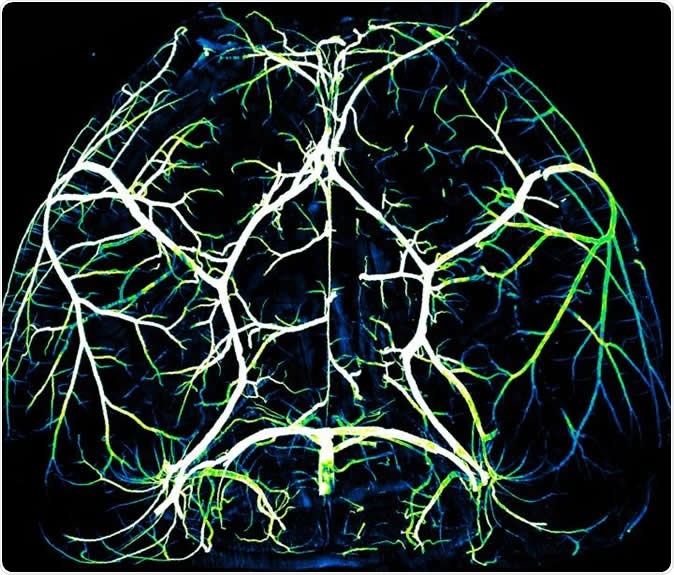

Arteries in the brain. Image Credit: Gu Lab/Harvard Medical School